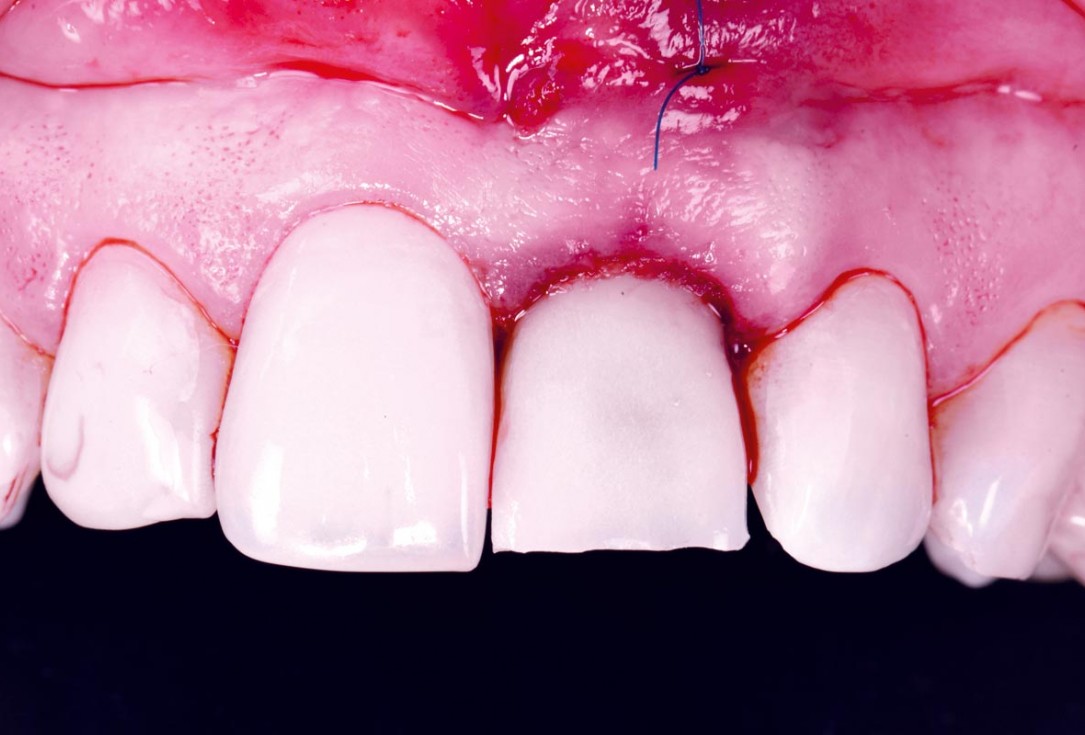

Covering of an immediately placed implant with permamem® - Prof. Z. Mazor

Immediately placed implant covered with permamem®. permamem® passively immobilized by sutures and intentionally left exposed to the oral cavity.